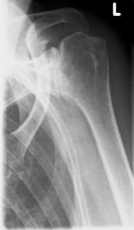

left: X-ray image of an omarthrosis

right: X-ray of a healthy shoulder joint